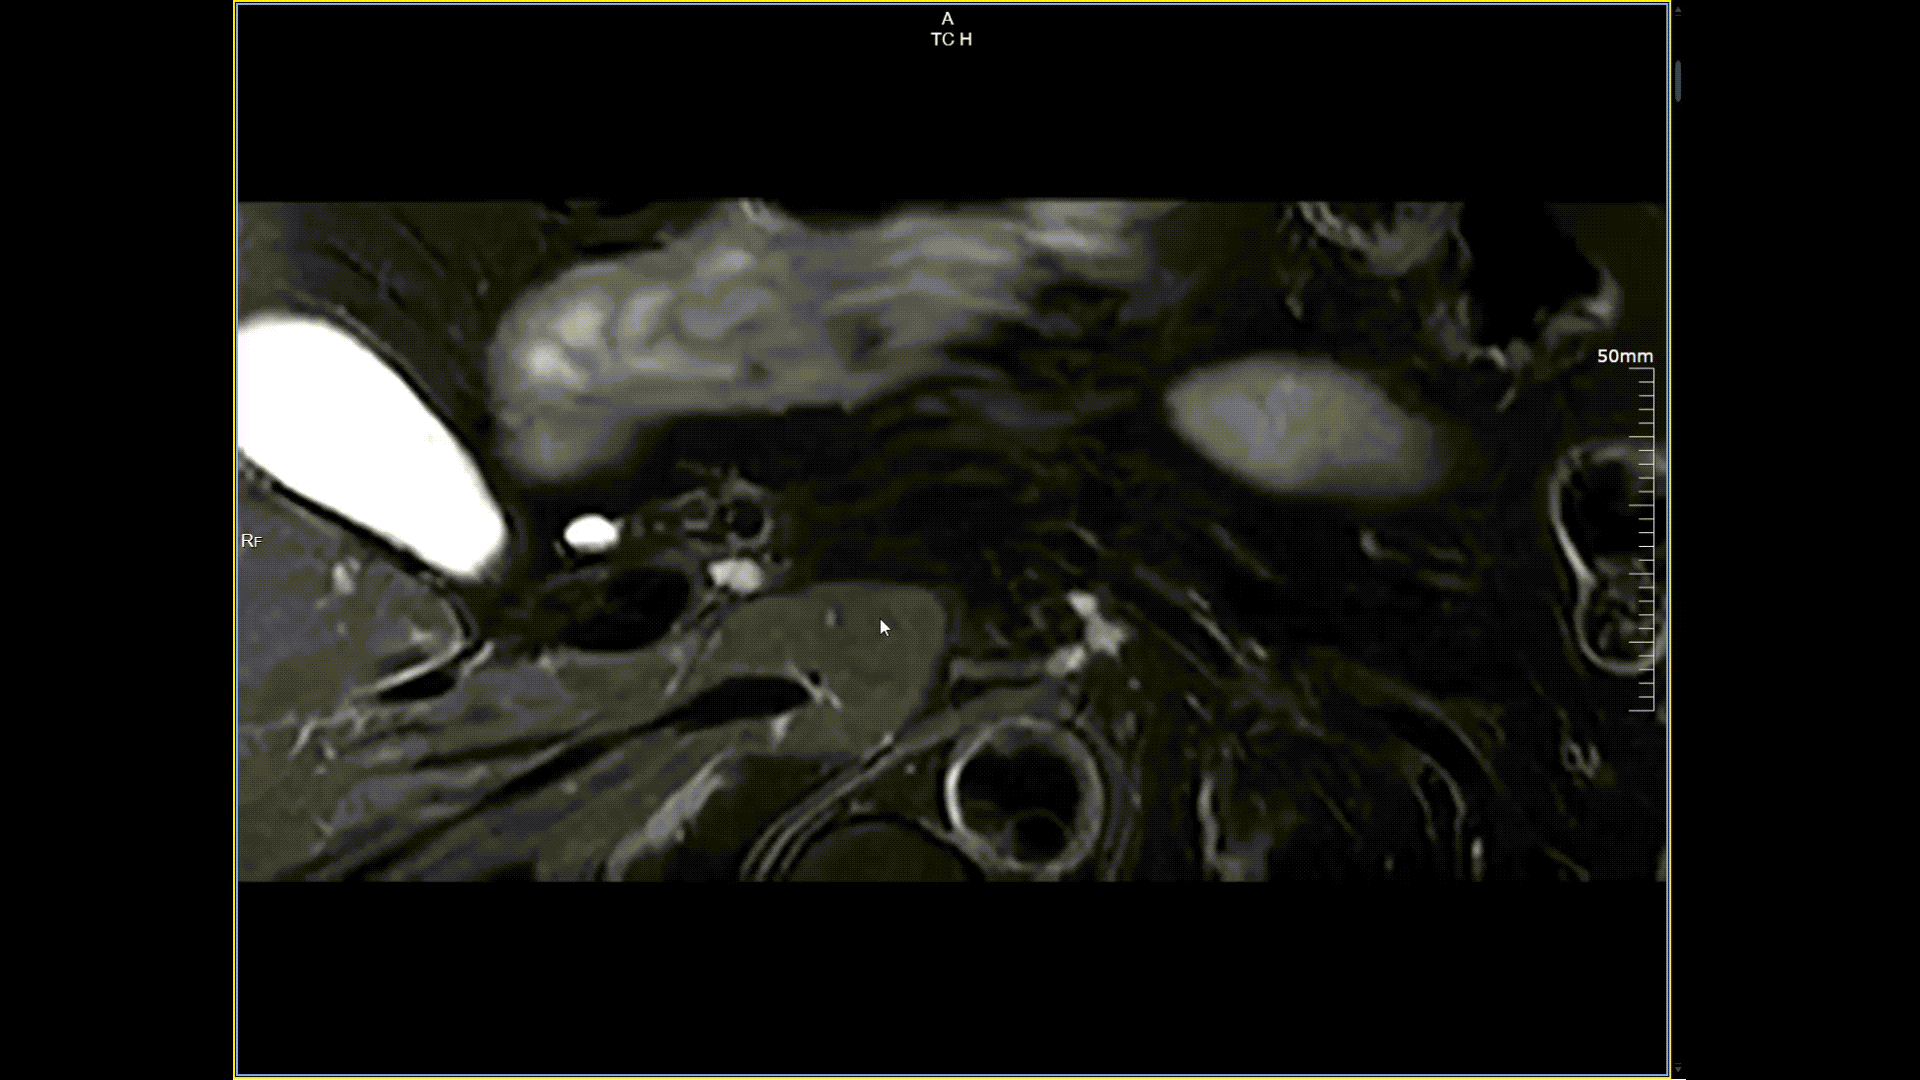

11月3日,一名30岁男性在我院接受了河北省首台5.0T超高场核磁共振头颅血管成像检查,图像清晰精准地反映出患者右侧小脑区域的血管畸形情况,该患者对我院的诊疗实力与服务温度给予充分肯定。相较于传统核磁共振,这台设备实现了“超高场全身各部位成像”的技术突破,它以业界领先的超高性能实现亚毫米级超高清成像,尤其在神经、心血管、体腹、关节等部位肿瘤疾病的早期发现、精准评估、个性化治疗方案制定中提供了的强大影像支持,将为全省乃至周边地区患者带来更优质、更精准的医疗服务。

5.0T磁场强度远高于其他设备,使得氢原子核在磁场中的响应信号极大地增强。这就像在安静的房间里能听清细微的声音一样,高信噪比能让医生看到更微小、更模糊的病变结构。例如上述患者的检查,该设备可以呈现0.2x0.2毫米高分辨率的图像以及动态显示血管走行,使得病变血管的细微解剖结构、分布及其与周边脑组织的关系得以直观呈现,为临床医生进行精准诊断并制定后续治疗方案提供了重要的影像学依据。

磁敏感成像SWI,分辨率0.2*0.2mm